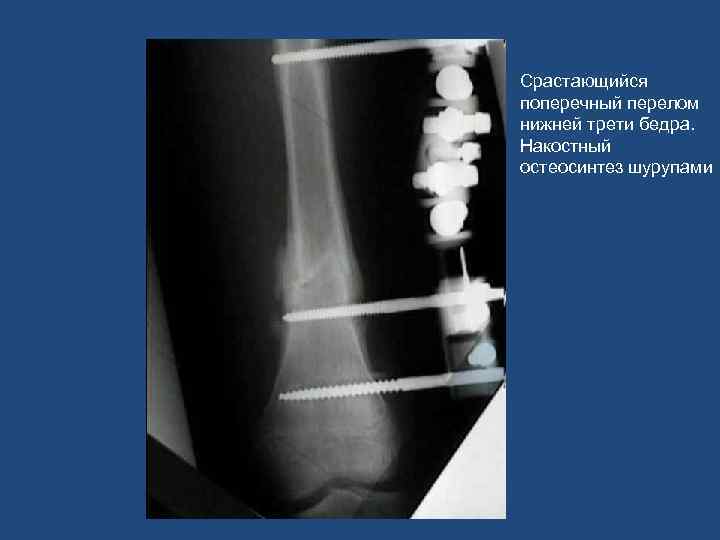

Срастающийся поперечный перелом нижней трети бедра. Накостный остеосинтез шурупами